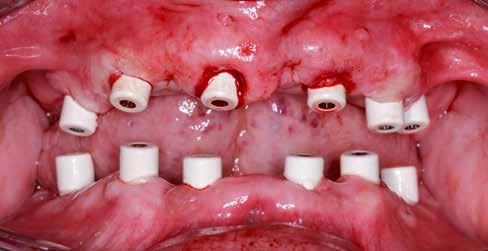

Hagyományos teljes fogsor hatékony átalakítása

Teljes ívű rehabilitáció primer vázra ragasztott lítium-diszilikát szekunder koronákkal